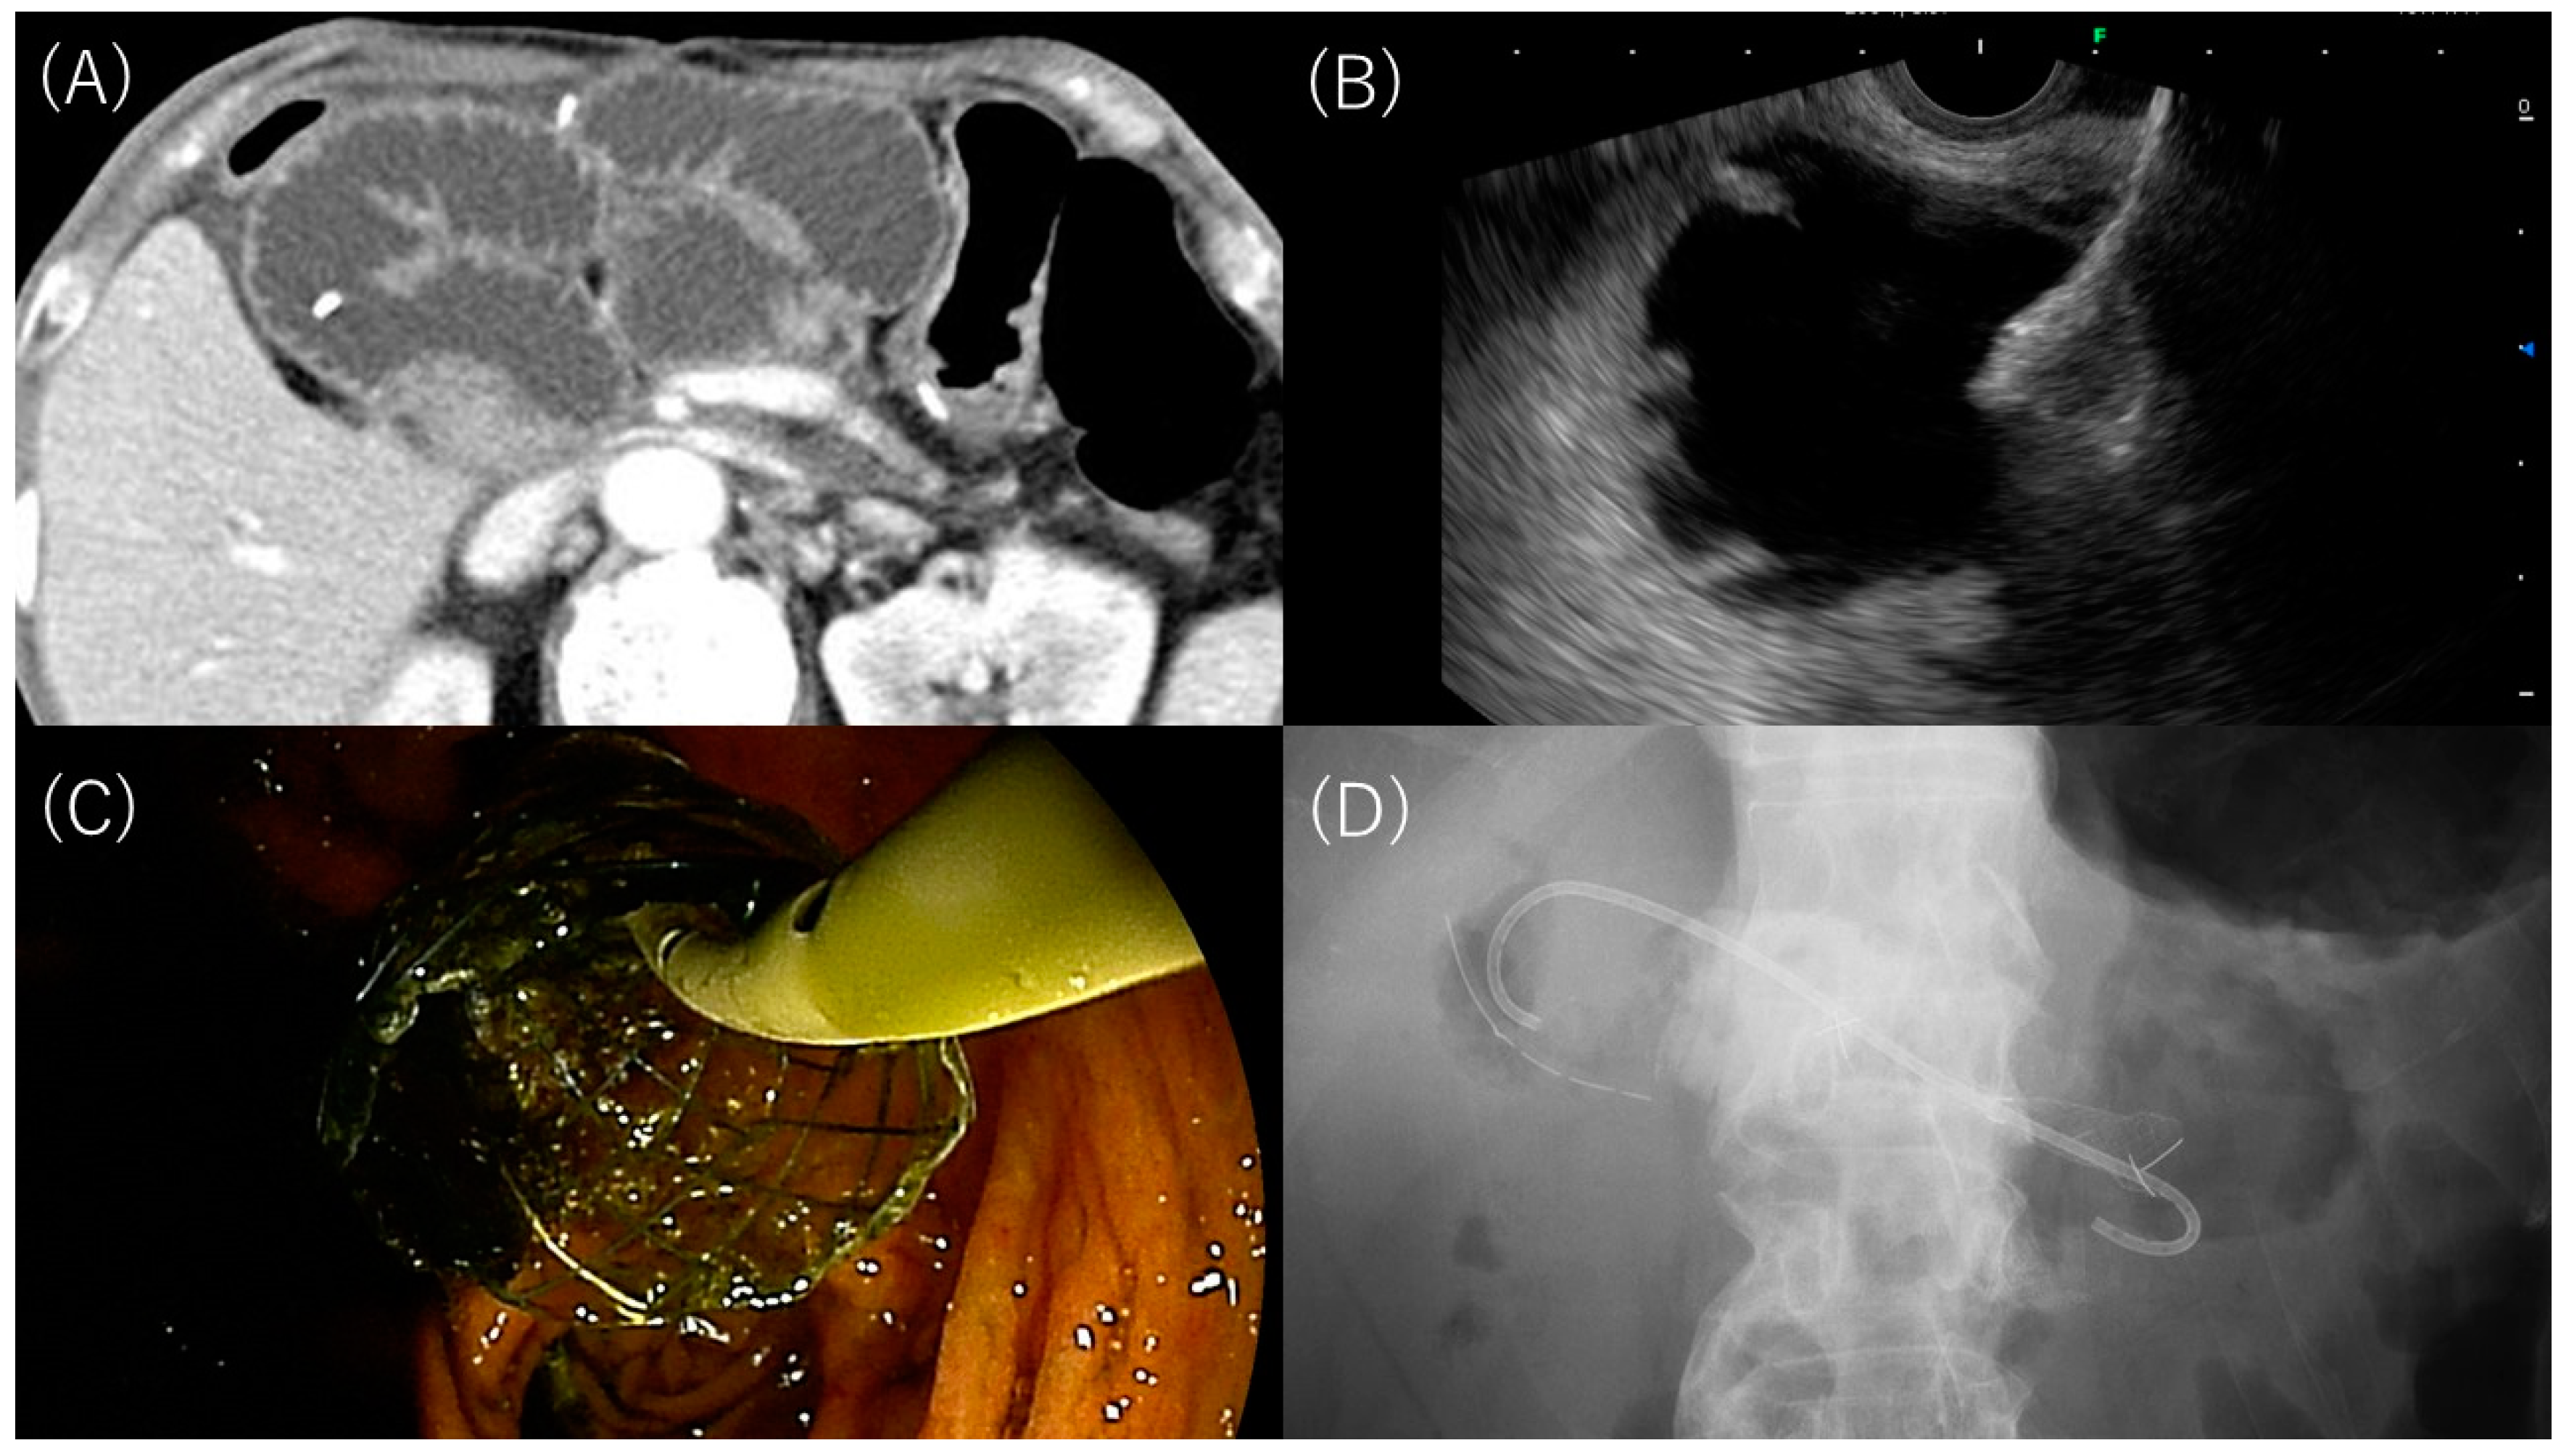

3.2. EUS-Guided Gastrojejunostomy